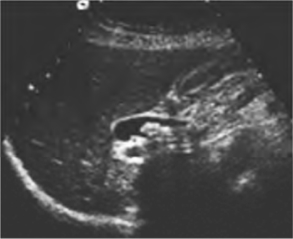

1.肝外胆管结石(图25-12) 肝外胆管扩张,内有团状强回声,后伴声影,与胆管壁有明确分界,部分有胆管壁增厚,回声增强。

图25-12 肝外胆管结石声像图